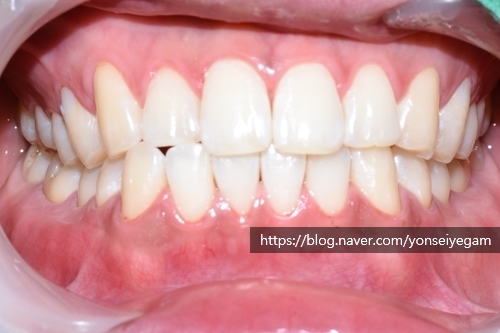

아래는 첫 날 치료(스케일링, 치아패인곳 떼우기, 원데이2회미백 진행)의 전&후 사진입니다.

같은 날 치료 전 후 다시 비교해 볼게요

당일 스케일링,화살표패인곳떼우는치료,미백2회 치료

색상의 변화가 보이시죠!

이날 원데이 2회 진행하신 모습입니다.

한시간 내외 시간만에 스케일링,레진,미백2회를 하고 이렇게 밝아지다니 놀랍죠?

만약 원데이 3회미백 진행하셨으면 더 밝아지셨을 것 같네요.